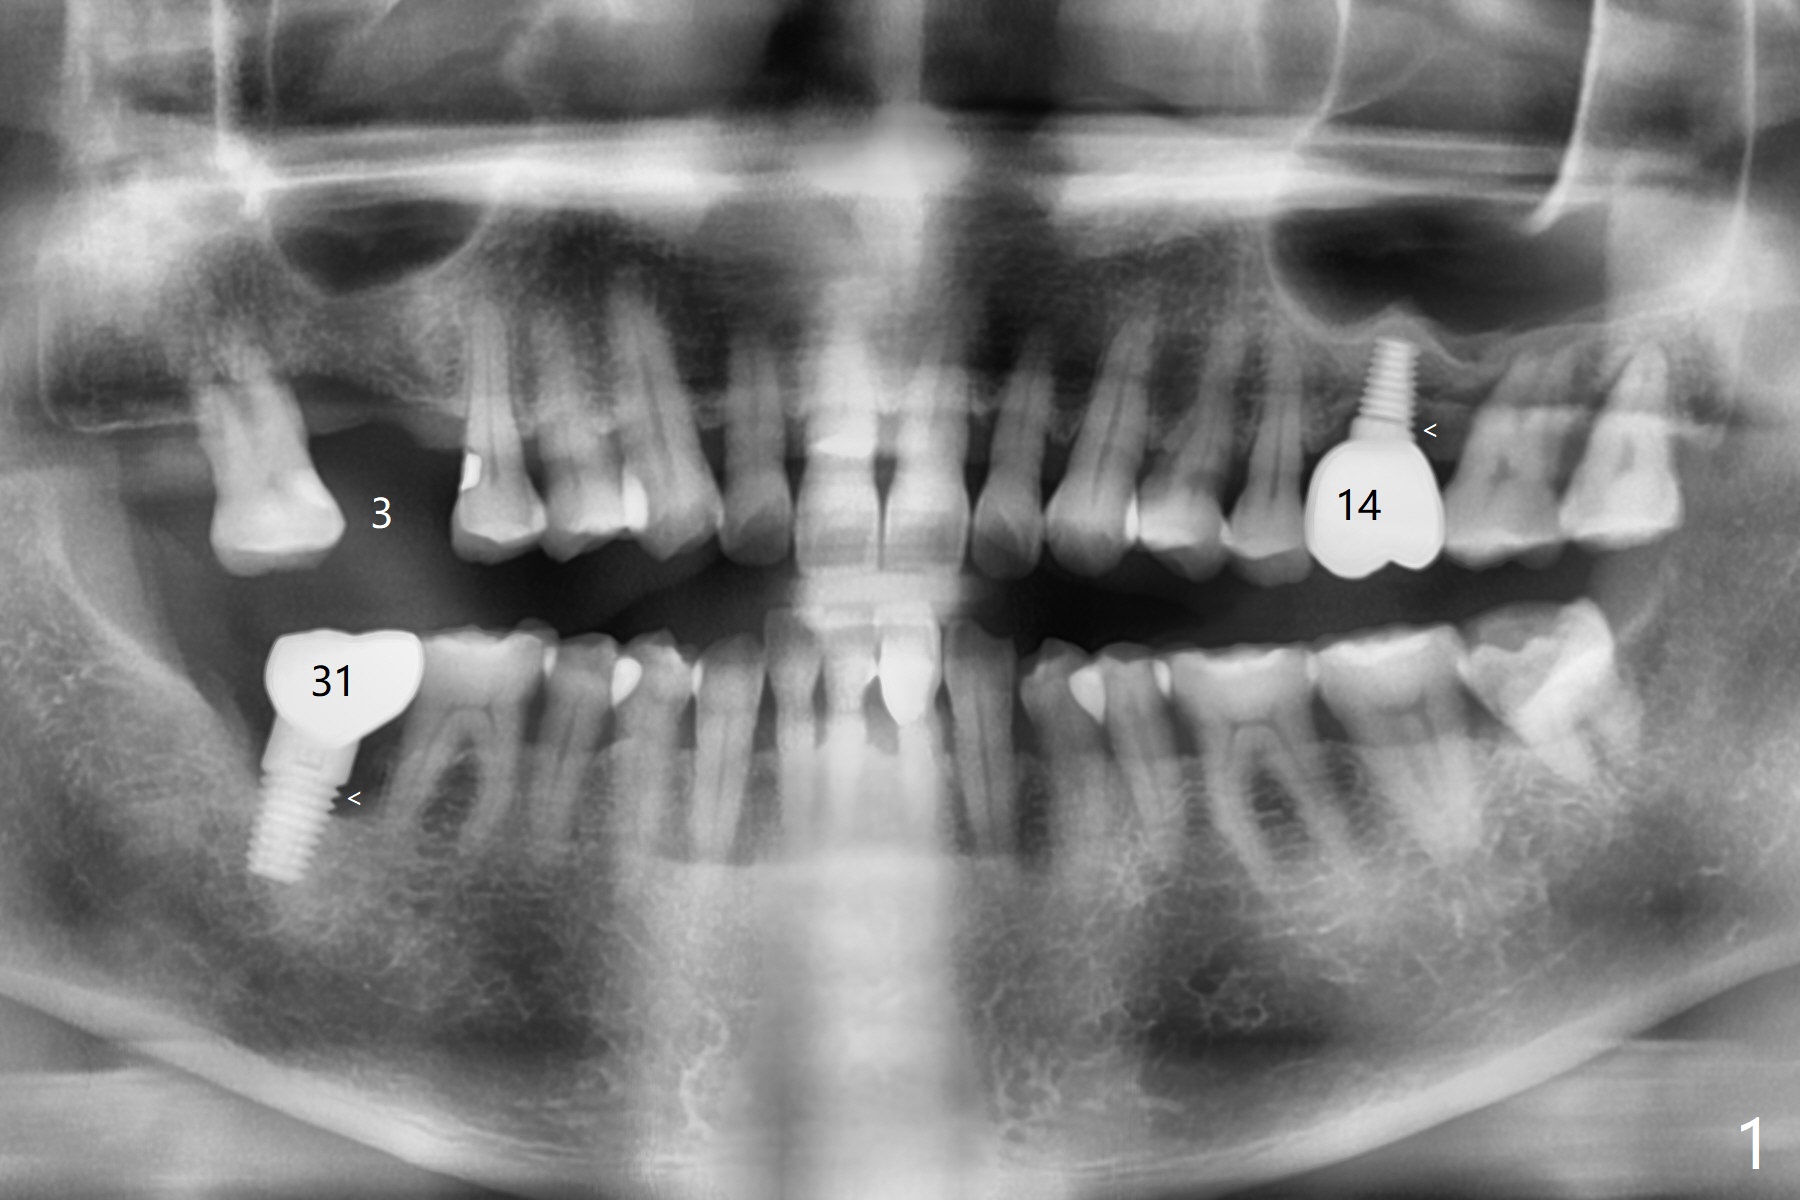

A 66-year-old man returns for #3 implant 1 month post #14 cementa-tion (Fig.1). The latter was placed free hand because of emergency (tooth fracture). The distal threads are exposed (<) probably related to shallow placement (imprecision) or insufficient bone graft. In spite of the wide ridge at #31 (data not shown), there is bone loss around the extremely large implant (<). In contrast, the ridge at #3 is narrow (Fig.2). A small implant (4x11 mm tissue-level) will be placed precisely in depth and position relative to the ridge with guide.